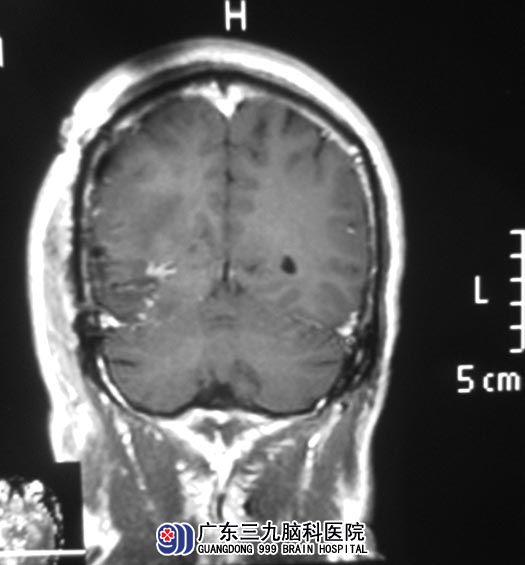

完善检查后,鲁明主任主刀,在唤醒麻醉下行右侧枕叶占位切除术,术前给予导航定位肿瘤并标记,术中再次导航定位肿瘤,显微镜下见肿瘤呈灰黄色浑浊样,血供一般,质地软,边界稍清,予肿瘤全切,手术顺利。术后温先生感觉右侧视野明显好转,未出现肢体等功能障碍。病理结果为:胶质母细胞瘤(WHO IV级)。

▲手术后